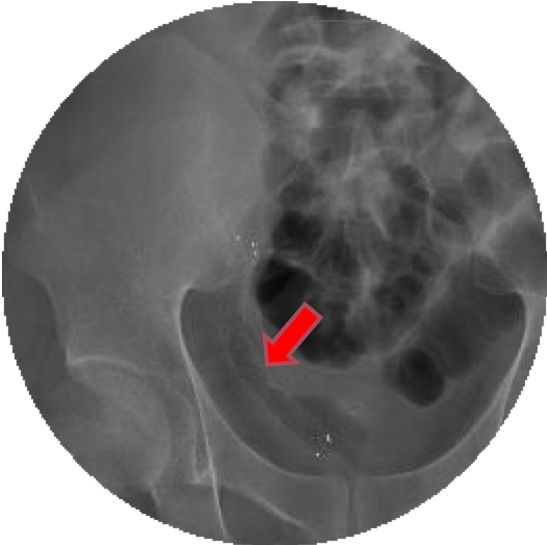

手术过程中,魏鑫副教授凭借娴熟的临床技艺及丰富的临床经验,迅速找到了异位在膀胱右侧顶壁的移植肾输尿管开口,并对狭窄做出了判断:

吻合口处明显狭窄,开口方向背向尿道内口,使用弯头超滑导丝可成功插入,但仅容2根超滑导丝并排通过。

插管造影显示,狭窄段长度约1cm,使用球囊扩张器扩张狭窄段后输尿管镜可以顺利窥察至肾盂。

短短一个小时,随着金属覆膜支架在输尿管内缓缓张开,狭窄段消失,造影显示输尿管通畅,肾积水迅速减少,手术成功。术后半小时尿量即达200ml,患者的“肾”命通道被顺利打通!

通过CT对比,术后第1天小庞移植肾积水显著减少(基本消失)。再看术后第三张CT,覆膜金属支架在位且支架重建“肾命通道”稳固通畅。